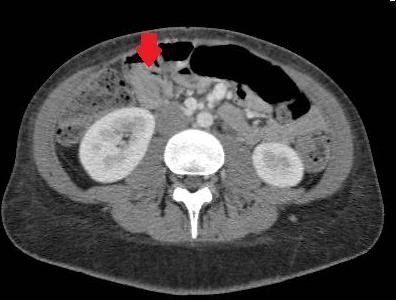

Na tomografia computadorizada é possível visualizar no plano axial as camadas duplicadas do intussuscepto e intussuscepiente, formando anéis concêntricos, sendo tal achado característico do “sinal do alvo”, descrito na ultrassonografia. No plano coronal, possivelmente pode ser visualizado a imagem conhecida como “salsicha“ de tecido mole. No exame contrastado a porção proximal da instussuscepção realçará dois anéis concêntricos. Esse achado equivale as paredes do intestino interno e a borda do intestino externo. À medida que a imagem avança pela tomografia, o mesentério formara um crescente de tecido comprimindo o lúmen interno.